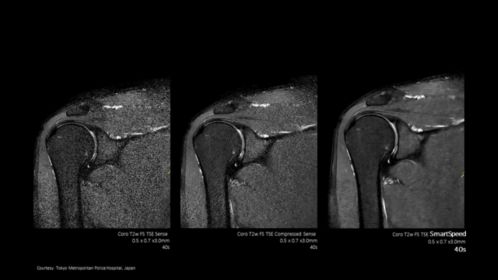

L’application Philips SmartSpeed met la qualité et la vitesse d’image à portée de main. Elle utilise le moteur d’accélération Compressed SENSE pour réduire le temps d’acquisition et applique un algorithme d’IA primé directement au début de la chaîne de reconstruction IRM, afin d’optimiser les informations et la qualité d’image pour l’imagerie ostéo-articulaire. L’application Philips SmartSpeed peut être utilisée en 2D et 3D, ainsi que pour tous les contrastes anatomiques. Elle prend en charge 97 % des protocoles IRM cliniques actuels* pour répondre aux besoins en imagerie de la plupart des patients.